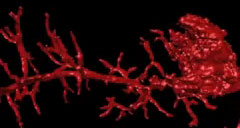

Extracción de cálculos complicados de las vías biliares con el sistema de visualización directa SpyGlass®

En este video se explica la técnica de extracción guiada por colangioscopía de cálculos complicados de las vías biliares.